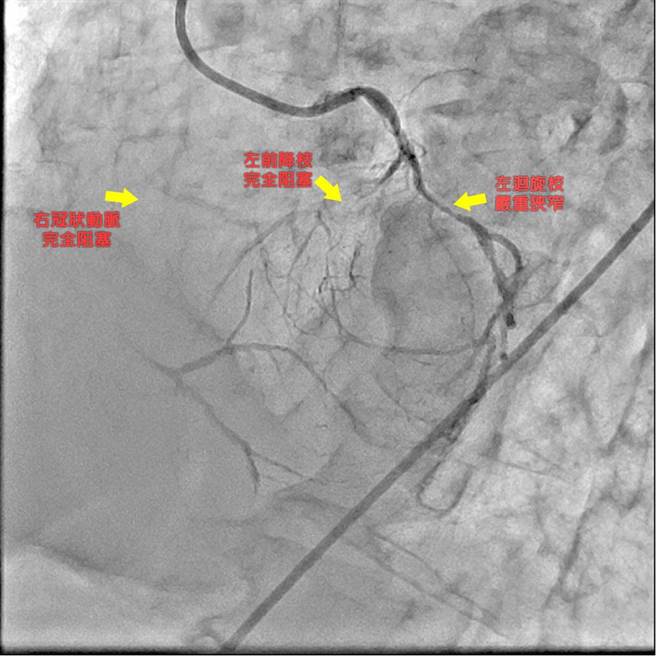

68岁从事铁工的男子日前上腹阵痛、噁心想吐,起初以为是急性胃炎,仅服用胃药却无缓解,工作中因呼吸困难、全身无力送往急诊,发现该男子心臟冠状动脉2条完全阻塞、1条严重狭窄,心肌梗塞发作,幸经心臟内外科团队合作进行心臟血管绕道手术,成功抢回生命。

孙德光表示,做工辛苦人生活及收入不稳定,极少接受健康检查又没有稳定控制其三高慢性病,且香菸不离口;这位患者到院时,已因呼吸困难、心跳急促几近休克状态,其心臟功能射血指数(EF)仅22%(正常应>50%),显示出现严重心臟衰竭,团队立即给予呼吸器支持,置入主动脉帮浦协助支持其心臟衰竭的危险。